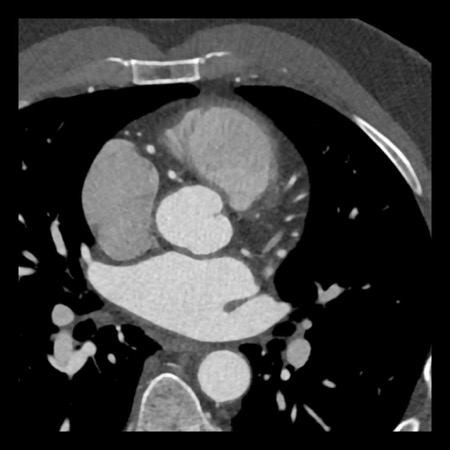

case 1 – CAD-RADS 2/P1

First, scroll through the scan.

Not all images are included. Some images without any abnormalities are skipped

from the series.

How would you describe the findings on the coronary CTA?

The findings are:

- Agatston score of

this patient was 14 (P1). Please, also note the calcification of the aortic valve. - Some partially

calcified and calcified plaques are present in the LAD with mild stenosis

(25-49%). - Calcified-plaque in

the LCX causing minimal stenosis (<25%). - Non-calcified

plaque in the distal RCA causing minimal stenosis (<25%). - This patient classifies

as CAD-RADS 2/P1, which means no further workup is needed.